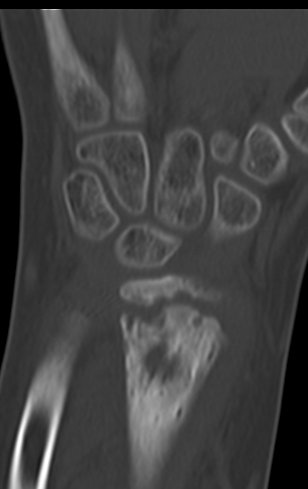

Después de una semana, el 14/08/2015, se retiró la férula y se encontró edema residual en la muñeca y dolor local. La semana siguiente, el 17/08/2015, fue evaluado por otro ortopedista quien repitió las radiografías y diagnosticó un quiste en el radio y una pequeña fractura arriba, figuras 1 a 5.

El domingo 20/09/2015, después de un día de mucha actividad física, caminar, nadar, se presentó aumento de edema y dolor en la muñeca derecha. Al día siguiente se realizaron nuevas radiografías de muñeca, que identificaron la evolución de la lesión, figuras 6 y 7.